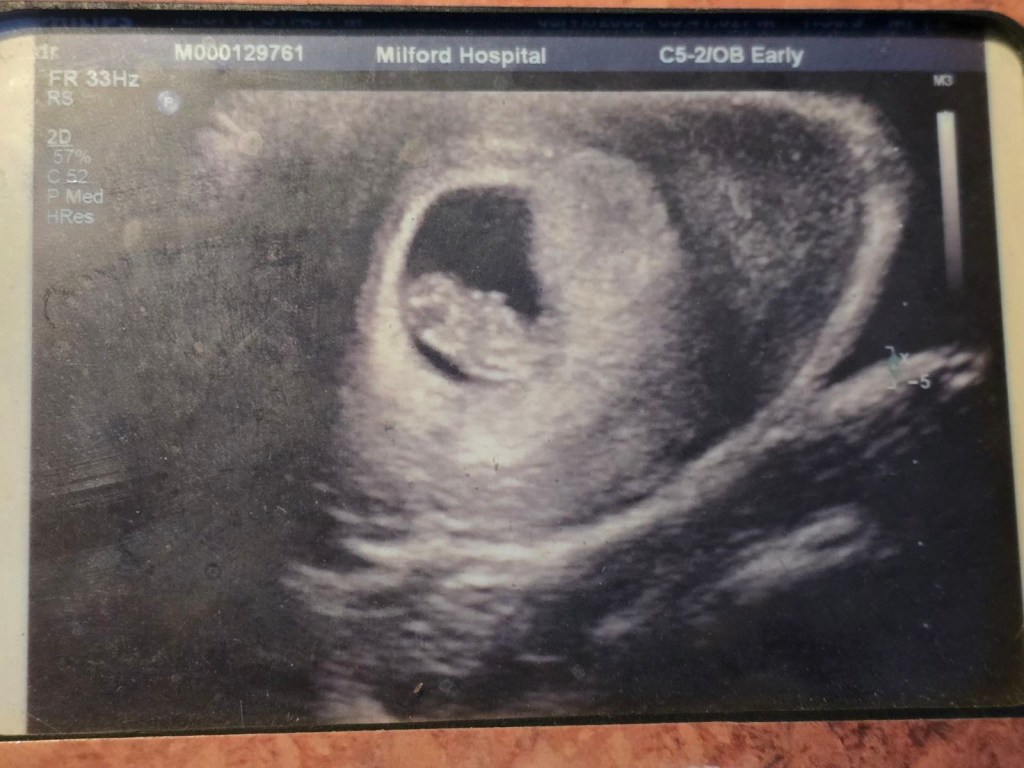

When Stacy was seventeen and Allen was twenty one, their lives completely changed forever. Stacy found herself at the hospital because of really bad stomach pains. Allen went with her to support her. They found that she was pregnant. It was a very shocking and intense moment for the young couple. They went home, and she immediately ran inside crying. Allen’s father was on the porch and immediately guessed that Stacy was pregnant and Allen confirmed his assumption. Allen’s father told him to go inside and comfort her, so he did. After a little while, Allens father went to talk to them and tell them, “What’s done is done, and we just have to get through it and deal with what is to come.” Ultimately, his father was supportive and helpful. This is not what Allen and Stacy planned, but Stacy believes that this is what was meant to happen. She isn’t religious by any means, but she feels as though the universe brought this to her for a reason.

Allen Edward Niper III was born at Milford Hospital. He was 8lbs, 6oz, and 22 inches long. Doctors estimated him to be about 6’6, which he is on track for. Allen was named after his father and his grandfather. His father’s name is Allen Edward Niper II, and his grandfather’s name is Allen Edward Niper. So to carry on the “legacy”, they named him Allen Edward Niper III. Stacy wasn’t as fond of the name, but wanted to make Allen happy, so she went along with it.